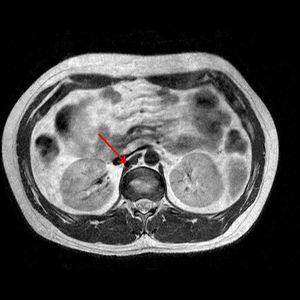

Exploración física normal salvo IMC: 32 kg/m2. Ecocardiograma, electrocardiograma y retina estrictamente normales. Hemograma, urea, creatinina, perfil hepático y lipídico, TSH, aldosterona, cortisolemia, actividad de renina plasmática (ARP) y sedimento urinario normales. ClCR (MDRD): 103 ml/min. Orina 24 h: 0,10 g prot, ácido vanilmandélico, metanefrinas, 5 OH indolacético normales. Ecografía Doppler renal: riñón derecho: 11,1 cm; riñón izquierdo: 13,2 cm; se detecta aumento de velocidad en arteria renal principal derecha (ARD) mayor a 3 cm/m, con ondas tardus parvus en segmentarias, sugiriendo estenosis de ARD mayor del 70%. Angiorresonancia: origen alto de ARD, con irregularidad y disminución de calibre en tercio medio, que se debe a anomalía en su origen, naciendo posterior y por encima de la inserción de crura diafragmática, por lo que debe atravesarla. Ante tales hallazgos se realiza arteriografía renal selectiva que confirma los hallazgos. Se realiza ACTP de la estenosis con buen resultado morfológico y clínico (presión arterial normal sin necesidad de medicación).

Figura 2. Angio-RM de arterias renales: origen anómalo de arteria renal derecha, con persistencia de la tortuosidad y estenosis en el tercio superior, secundarias a su paso a través de la crura diafragmática